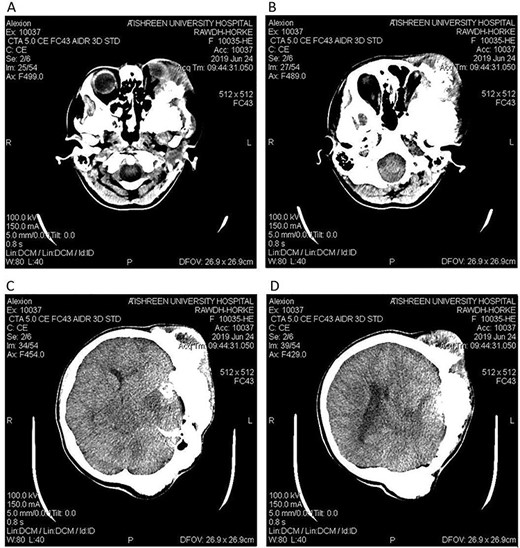

CT head tissue window (A, B). A. Invasion of the maxillary sinus and orbit. B. Invasion of the parietal, temporal and frontal lobes. A remarkable exophthalmos. Bone window (C, D). C. The bone-forming lesion showing the same density of the bone. D. Invasion of the sphenoid, temporal and parietal bones.

A 17-year-old female presented with a history of osteosarcoma that was confirmed after undergoing a surgery to remove an enlarging bone tumor in the left temporal region 2 years ago. She later got pregnant and delivered her child but never got back for a checkup until she was admitted to our hospital with a severe and unresponsive to medication headache that progressed over the course of 6 months and blurred vision that progressed to complete left-sided vision loss. Physical examination revealed a tough and mobile yet fixed at the base 7-cm mass towards the left of the frontal bone. Many more masses were revealed in the left side of the skull including the anterior cranial fossa, orbit, base of the skull and the left part of the occipital region where the previous procedure was performed (Fig. 1). These masses had been increasing in size probably under the influence of pregnancy hormones causing pain that radiated along the orbital and maxillary branches of the left trigeminal nerve. Physical examination and past medical history were otherwise unremarkable. Laboratory tests were all normal, and her family history was negative. Staging studies showed no evidence of distant metastatic disease in the chest, the abdomen and the pelvis. CT scan of the skull revealed a bone-forming non-lytic lesion accompanied by periosteal reaction. This lesion bulges to the outside towards the scalp spreading into both the soft tissues and the inside of the entire left side of the skull with a sunburst-pattern (Figs 2 and 3). Its rims are unsymmetrical and pointy, and it bulges into the left orbit outside the muscles causing exophthalmos with a semi-complete proptosis of the eyeball out of the orbit (Figs 2 and 3). This lesion applies pressure to the left frontal and temporal lobes causing mild edema in both these lobes without invading the brain tissue. This edema in turn applies pressure to the left lateral ventricles (minor shift of the elements of the midline to the right side can be seen on CT) (Fig. 4). Due to the tumor’s wide spread, the surgical procedure was performed in two stages (approximately 6-hour-long each). In the first stage, the bone mass was removed through a procedure of wide skull approach including the frontal, temporal and parietal bones and a removal of the invading part of the temporal muscle. Moreover, the lateral wall and roof of the left orbit were removed, the left optic nerve was dissected free and part of the meninges was removed and replaced with an autogenic patch from the fascia lata. Then, the bone loss was compensated for by using bone cement Synicem VTP (poly methyl methacrylate and Barium sulfate), and the orbit was rebuilt; the eyeball was placed back with noticeable decline of the exophthalmos. In the second stage, a complementary left parietal occipital incision of the previous approach was performed 3 weeks later; the remaining of the frontal and occipital bones was removed, and a partial mastoid surgery was done. Furthermore, the cavernous sinus were revealed and found to be not invaded. Later on, the normal skull shape was restored using the same cement. The histopathology of the lesion revealed proliferation of neoplastic chondroblasts, osteoblasts and spindle-shaped cells. The features are consistent with low-grade chondroblastic osteosarcoma (Fig. 5). The patient did not need ICU admission. She recovered well 3 days after the surgery and was discharged with no deficits. A CT scan that was performed post-operatively revealed that the masses were successfully excised (Figs 6 and 7). At the last follow-up 1 month post-operation, the patient was scheduled to undergo a course of radiotherapy, 60 Gy of radiotherapy in 30 fractions over 4 weeks without chemotherapy, as it is not recommended with low-grade osteosarcoma.